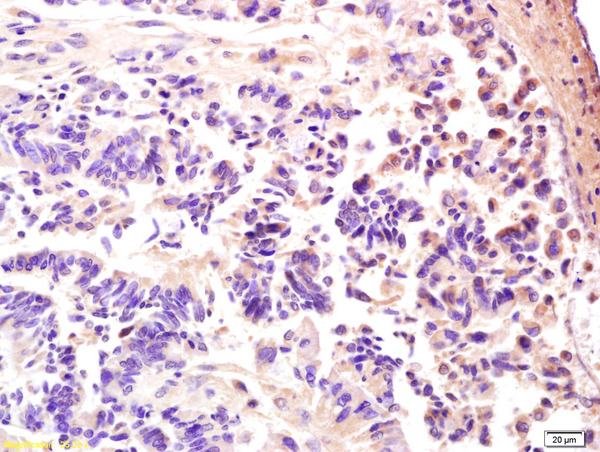

IHC-P analysis of human rectal carcinoma tissue using GTX51582 AMPK gamma 3 antibody.

Dilution : 1:200